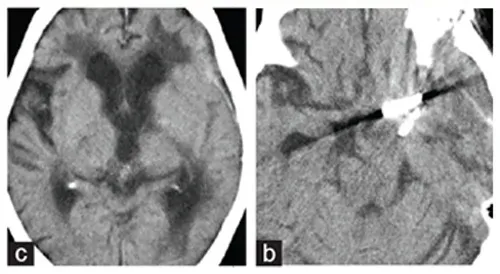

术后第二天,王叔的意识就明显好转;两周后,复查显示:动脉瘤完全夹闭,血栓清除干净,脑干压迫解除!

他的格拉斯哥昏迷评分(GCS)达到满分15分,意识完全清晰;右侧偏瘫逐渐改善,动眼神经麻痹也部分恢复。

术后CT显示,脑干解除占位效应,无缺血性病变